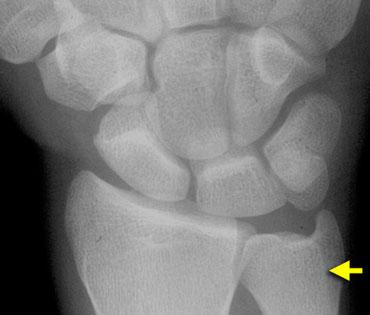

Phân tích:

1. Mất tính song song tại khớp LT (nguyệt-tháp) dẫn đến gián đoạn cung I và II.

2. Xương nguyệt và xương thuyền song song với nhau nhưng không song song với các xương cổ tay còn lại.

3. Xương thuyền bị ngắn lại do nghiêng về phía lòng bàn tay (palmar tilting).

4. Xương nguyệt song song với xương thuyền. Vì vậy, hình dạng tam giác phải là kết quả của việc nghiêng về phía lòng bàn tay.

5. Hàng cổ tay gần không phải là một khối thống nhất vì cung I bị gián đoạn.

Tư thế nghiêng cho thấy sự nghiêng về phía lòng bàn tay của xương nguyệt, điều đã được nghi ngờ trên tư thế PA.

Chẩn đoán cuối cùng:

VISI kèm phân ly tại khớp LT (nguyệt-tháp).